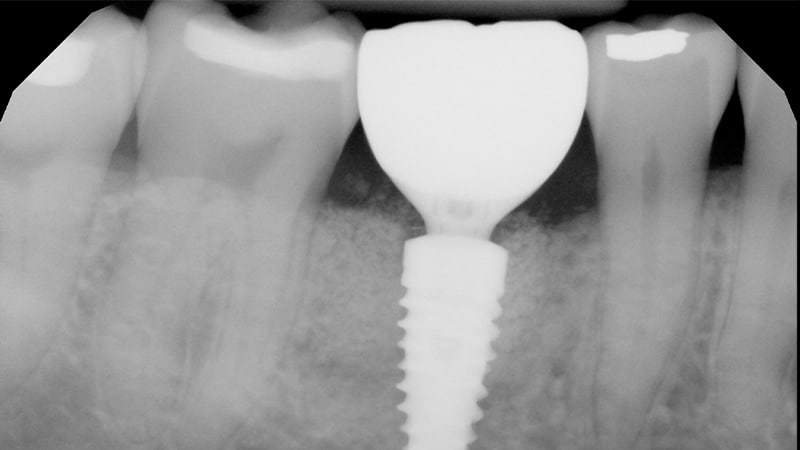

Natural teeth are comprised of two distinct parts: the crown that shows above the gumline, and the roots that anchor them in place. Traditional tooth replacements like dental bridges and dentures can easily fill the visible gap in your smile, but they can’t do anything to replace the missing root structure. Alternatively, dental implants are designed to rebuild missing teeth in their entirety for vastly superior results.

A dental implant is a small titanium post that is inserted directly into the jawbone just like the roots of a tooth. Atop the dental implant is a small connector piece called an abutment, which secures the custom-made restoration. Depending on how many teeth are missing, one or more dental implants can support a dental crown, bridge, partial, or full denture for a complete smile. This unique placement allows the patient to speak, chew, laugh, and smile with complete confidence in their new teeth!